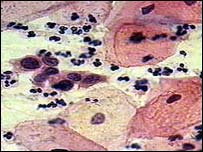

تصويری از يک نمونه در آزمايش پاپ اسمير

• آزمايش پاپ اسمير (Papanicolaou Smear)- الگوی غربالگری سرطان گردن رحم جهت تشخيص پيدايش ياخته‌های پيش سرطانی و سرطانی، رديابی انواع عفونتهای ناشی از باکتری، قارچ و ويروس در نواحی گردن رحم و مهبل است. آزمايش پاپ اسمير پس ازشروع فعاليت جنسی سالی يک بار و پس از دو تست منفی هر ۳ سال يک بار تکرار می‌شود. اين آزمايش معمولاً دو هفته پس از اتمام عادت ماهانه و حداقل ۴۸ ساعت پس از مقاربت جنسی توصيه می‌شود. پس از نتيجه مثبت آزمايش پاپ اسمير و مشاهده ناهنجاری ياخته های گردن رحم، اقدام بعدی بررسی کولپوسکوپی (Colposcopy) گردن رحم است که بزرگنمايی 8 تا 40 برابر ياخته را امکانپذير می کند.